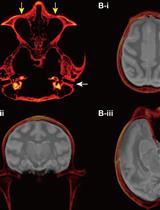

通过手持式注射将化学遗传学腺相关病毒载体靶向递送至猕猴皮质沟区域

Targeted Delivery of Chemogenetic Adeno-Associated Viral Vectors to Cortical Sulcus Regions in Macaque Monkeys by Handheld Injections

KO Kei Oyama

YN Yuji Nagai

TM Takafumi Minamimoto

1694 Views

Dec 5, 2023

Recent advancements in chemogenetic tools, such as designer receptors exclusively activated by designer drugs (DREADDs), allow the simultaneous manipulation of activity over a specific, broad brain region in nonhuman primates. However, the introduction of DREADDs into large and complexly shaped cortical sulcus regions of macaque monkeys is technically demanding; previously reported methods are time consuming or do not allow the spatial range of expression to be controlled. In the present report, we describe the procedure for an adeno-associated viral vector (AAV2.1) delivery via handheld injections into the dorsolateral prefrontal cortex (Brodmann’s area 9/46) of macaque monkeys, with reference to pre-scanned anatomical magnetic resonance images. This procedure allows the precise delivery of DREADDs to a specific cortical region.Key features• This article describes the procedures for injecting viral vectors encoding functional proteins for chemogenetic manipulation into targeted cortical sulcus regions.• The protocol requires magnetic resonance imaging for the accurate estimation of the injection sites prior to surgery.• Viral vector solutions are injected using a handheld syringe under microscopic guidance.• This protocol allows for the precise introduction of designer receptors exclusively activated by designer drugs (DREADDs) to large and complex cortical regions.